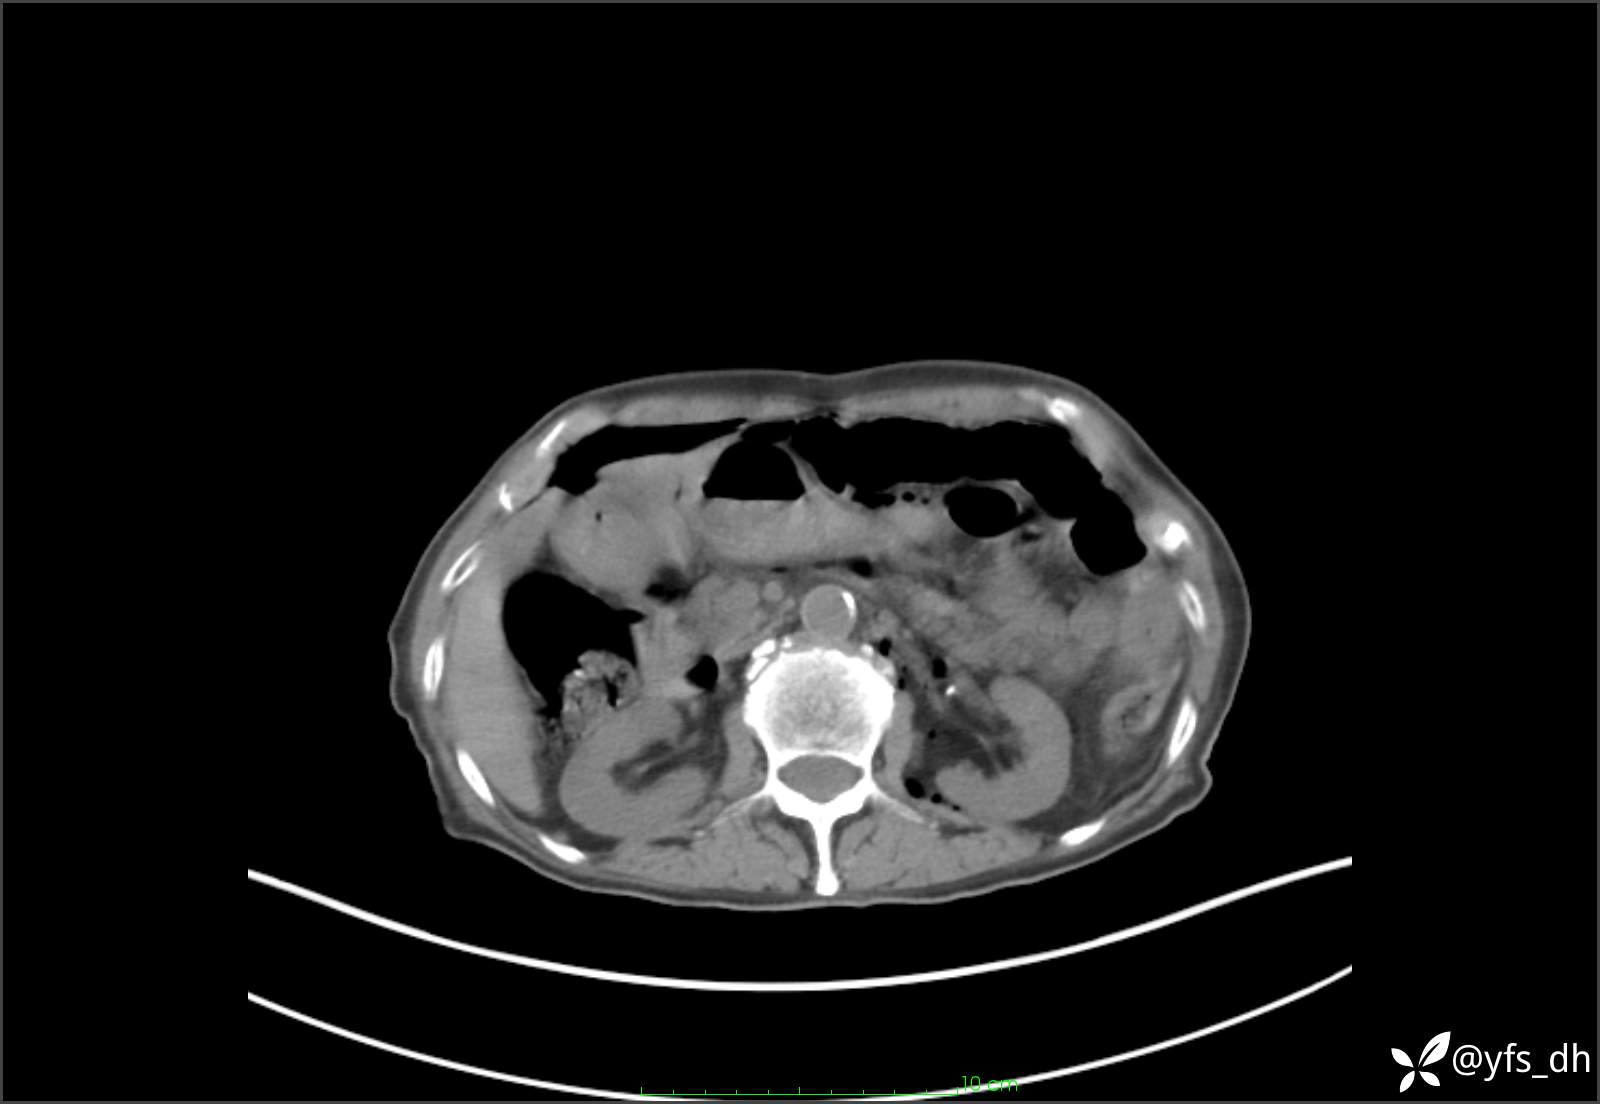

1.简要病史:患者4天前突发上腹部疼痛不适,但可以忍受。3小时前饭后突然加重,不能忍受后就诊。

2.简要手术记录:术中见腹盆腔大量肠液及粪便,乙状结肠中下段见一约3cm的破口。